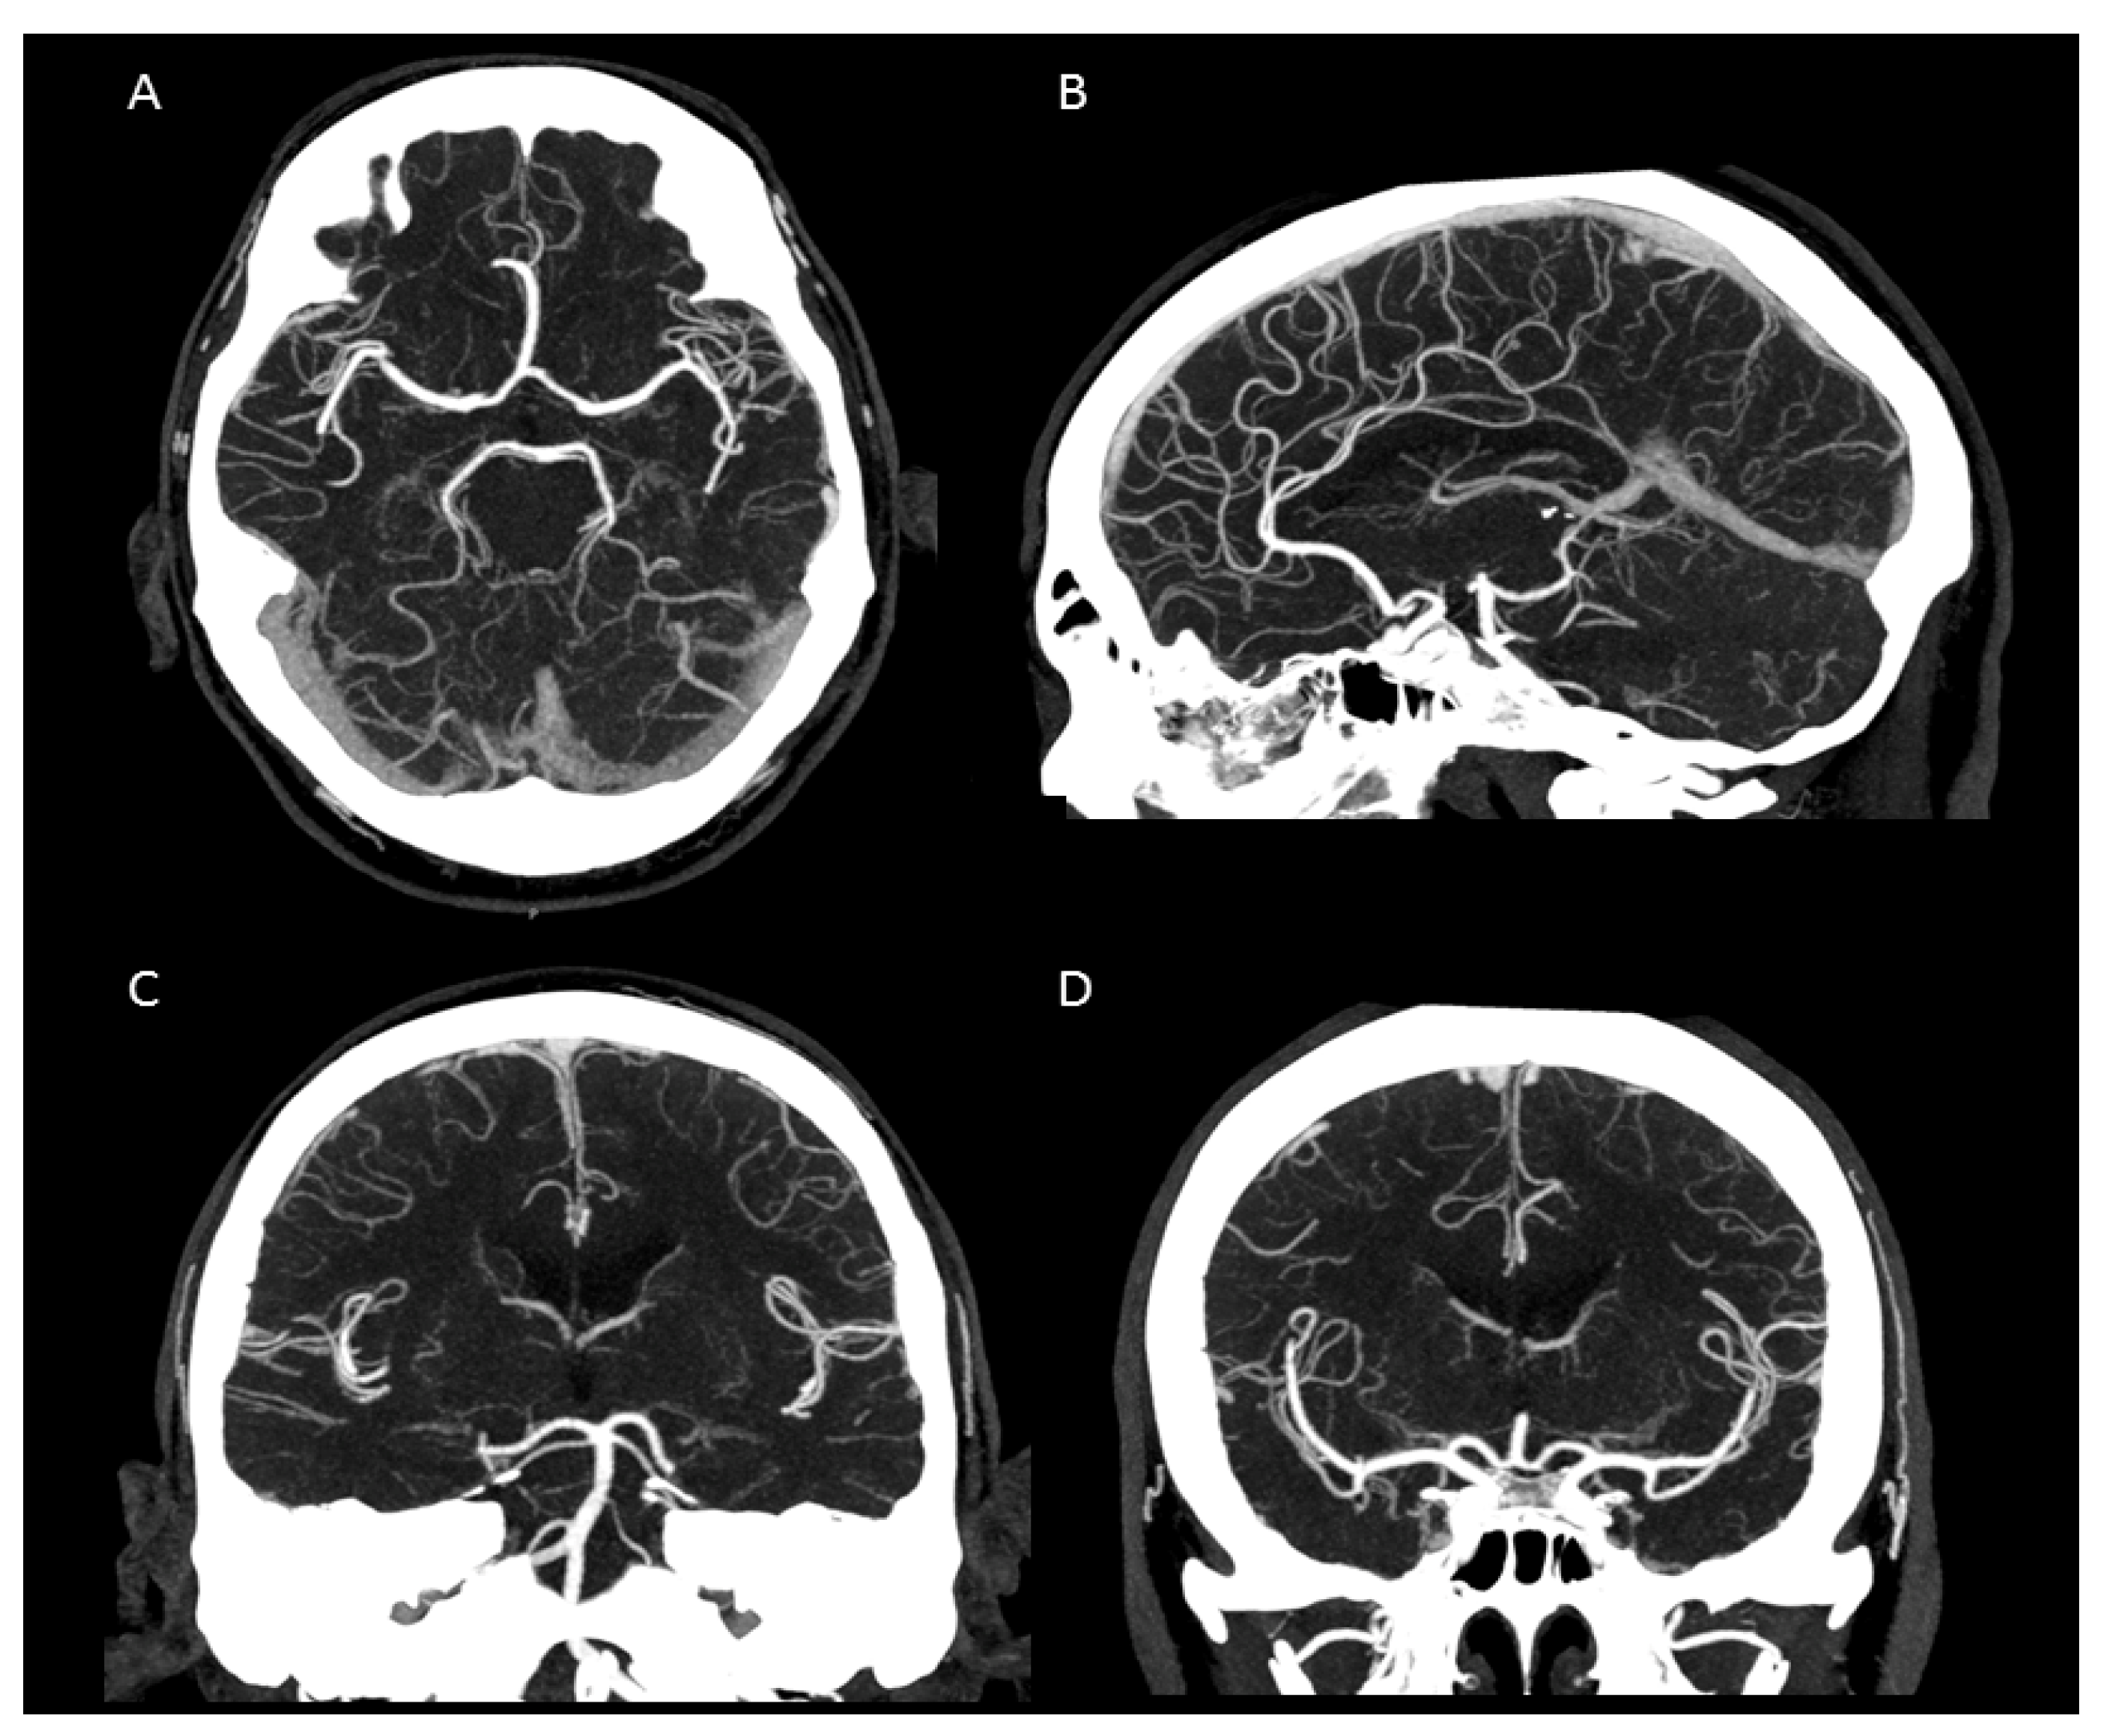

In summary, the subjective analysis of all images showed excellent results for the applied qualitative parameters such as overall image quality, overall contrast noise and artefacts, the latter focusing on streaks within the posterior fossa. A high-rated vessel contrast and delineation could also be observed, which were not only limited to the large cerebral vessels but also appeared in the smaller vessel sections, especially in the deep cerebral perforators (e.g., lenticulostriate arteries). Patient examples are given in Figure 2, Figure 3, Figure 4 and Figure 5. Interrater reliability was ascertained by applying Cohen’s kappa coefficient and showed a fair agreement (k = 0.26).

We were able to show that excellent image qualities were generated even though radiation exposure could be kept at explicitly moderate levels [10]. In addition, the occurrence of Hounsfield artefacts that frequently hinder the assessment of the vertebrobasilar system and the brainstem were also considerably low, enabling an advanced image interpretability. Both quantitative and qualitative evaluation of the UHR-CTAs confirmed our hypothesis of a highly remarkable improvement in image quality and spatial resolution. In particular, a high vascular contrast and a distinctly defined demarcation of the extracranial as well as the intracranial vessels could be demonstrated. It is noteworthy that even the smallest perforating arteries (e.g., LSA, as shown in Figure 3) vascularizing the deep brain structures become diagnostically accessible by UHR-CTA, which is generally not the case when using conventional CTA.

Figure 3. Maximum intensity projection of an intracranial UHR-CTA. (A) axial plane. (B) sagittal plane. (C,D) coronal plane. Note the clear traceability/visualization of the circle of Willis and even the small peripheral vessel branches.